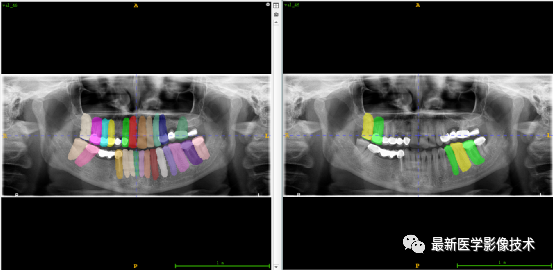

验证集牙齿分割计数和异常牙齿分割识别

左图是分割计数,右图是异常牙齿分割识别结果